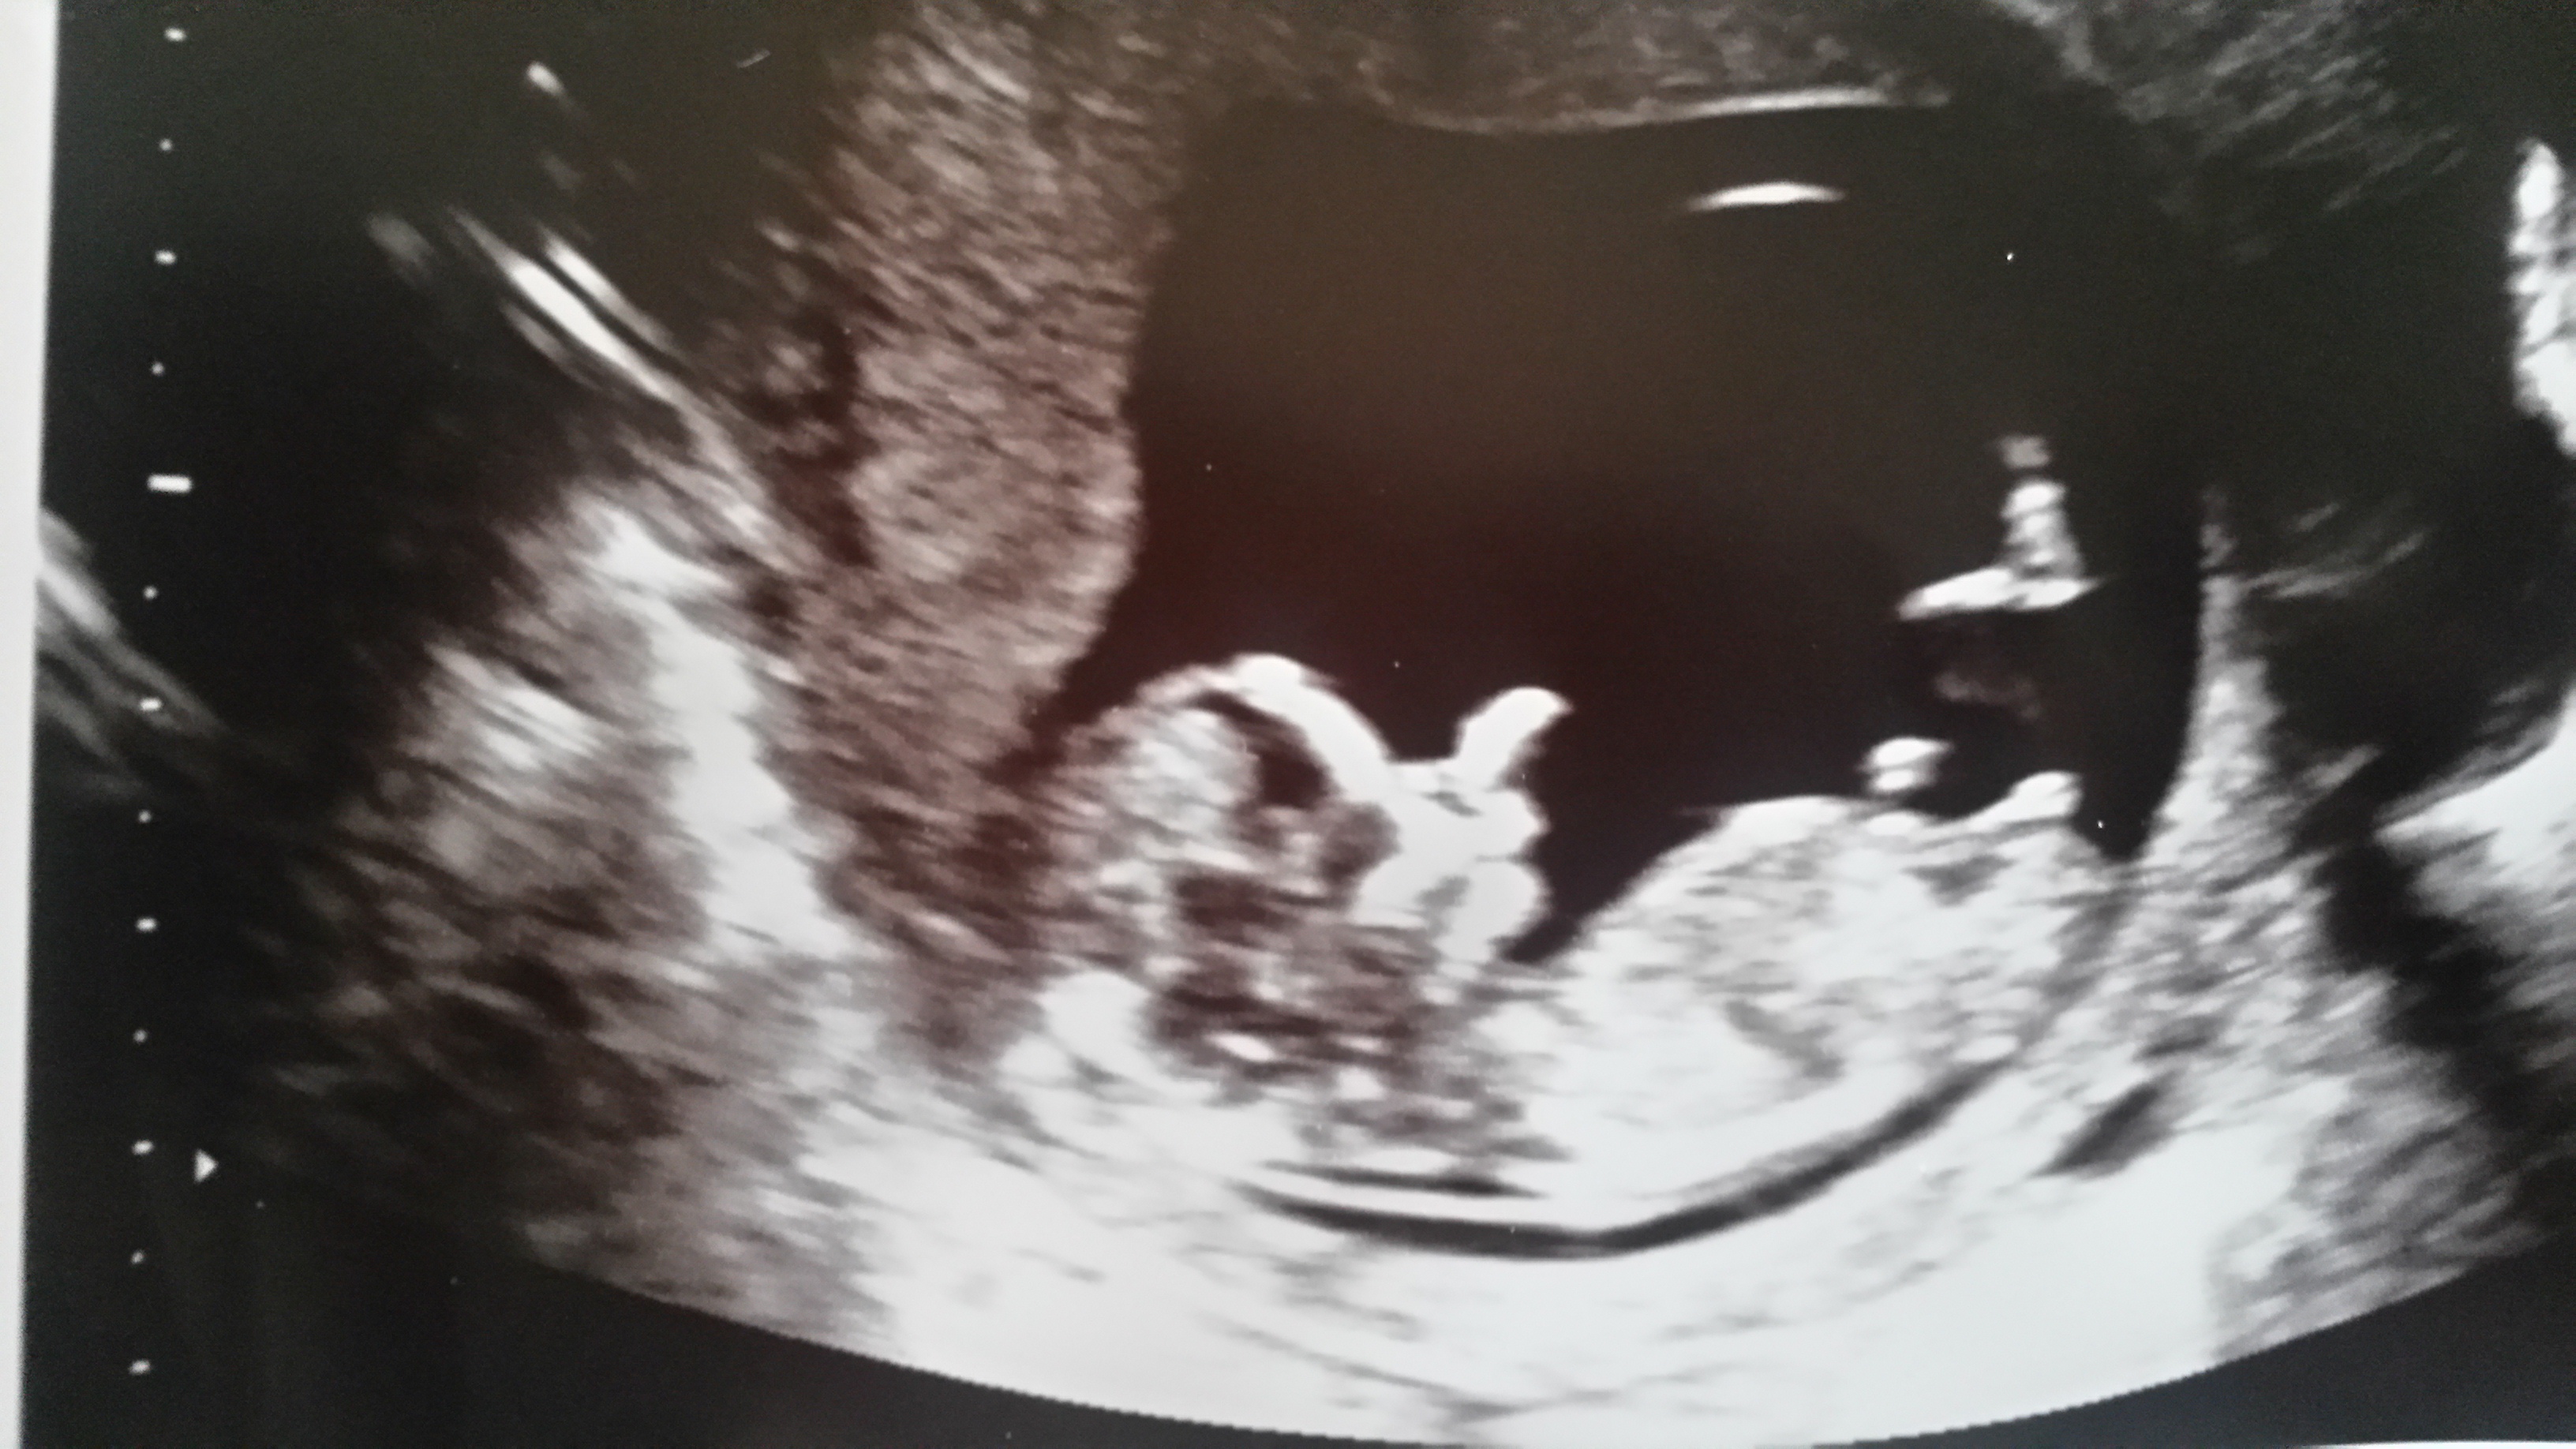

Any guesses? 12 w 4 days